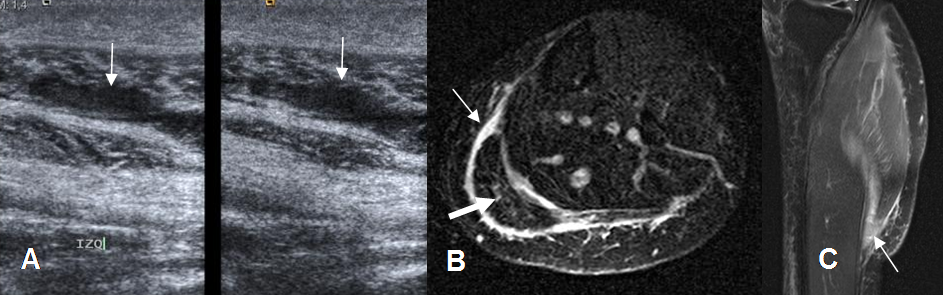

Fig 60. Lesión muscular grado II.

A: Ecografía longitudinal. Pérdida del patrón fibrilar del músculo, con líquido rodeando las fibras.

B: RM axial en STIR y C: RM sagital en STIR. Líquido perifascial (Flechas delgadas), con ruptura de algunas fibras del gemelo interno (Flecha gruesa), por lesión muscular G II.